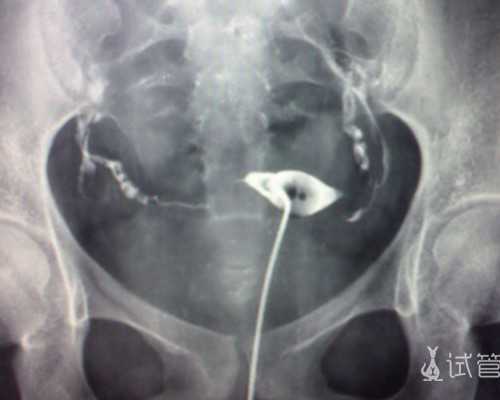

其实我们得到了一个好的胚胎,也并不意味着这个是试管婴儿手术就能够做成功了,虽说试管婴儿是在体外受精的,但是整个发育成长过程都在母体子宫,所以母体的子宫环境是尤为关键的,决定着胚胎有没有一个良好的发育环境,如果有一个良好的发育环境,胚胎才能够不断往好的方向成长,因此在一个优良的子宫环境当中,才能够保证胚胎不会产生变异或一些其他异常的状况,但因为很多不孕不育患者本身子宫是存在一定疾病的,那么就导致无法提供良好的子宫环境,此时大家需要到专业的机构进行治疗。